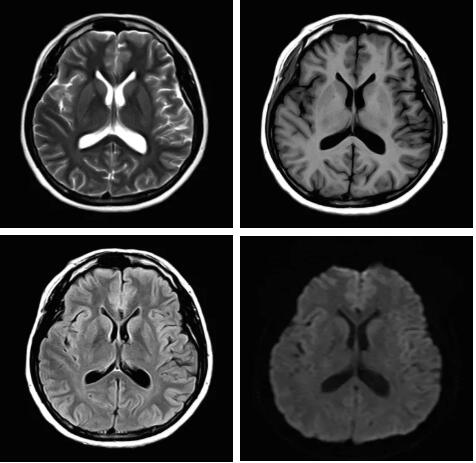

見(jiàn)所未見(jiàn) 微小腫瘤無(wú)處遁藏——

“螢火蟲(chóng)”成像技術(shù) 顱內(nèi)腫瘤微小病灶檢出新發(fā)現(xiàn)

此技術(shù)主要用于神經(jīng)系統(tǒng)惡性腫瘤,以及其他腫瘤腦轉(zhuǎn)移瘤篩查。傳統(tǒng)情況下做腫瘤腦轉(zhuǎn)移篩查,很容易漏掉5mm以下小病灶,臨床發(fā)現(xiàn)后干預(yù)治療比較晚,要實(shí)現(xiàn)2mm高空間分辨率和超薄層全腦掃描在保證信噪比的情況下需要很長(zhǎng)時(shí)間大概十多分鐘,而且薄層增強(qiáng)序列顱內(nèi)血管呈高亮信號(hào),會(huì)干擾顱內(nèi)小病灶的觀察,血管和小病灶區(qū)分困難。佳能”螢火蟲(chóng)”成像技術(shù)既可以實(shí)現(xiàn)高空間分辨率和超薄層(最薄可實(shí)現(xiàn)0.2mm)全腦掃描,掃描時(shí)間短,2-3分鐘即可實(shí)現(xiàn)全腦3D掃描,同時(shí)避免了血管高亮信號(hào)的干擾,對(duì)顱內(nèi)原發(fā)或繼發(fā)的微小腫瘤檢查有重大意義。“螢火蟲(chóng)”成像技術(shù)具有磁敏感效應(yīng),對(duì)于亞急性血敏感敏感,可以區(qū)分出血和強(qiáng)化的腫瘤。